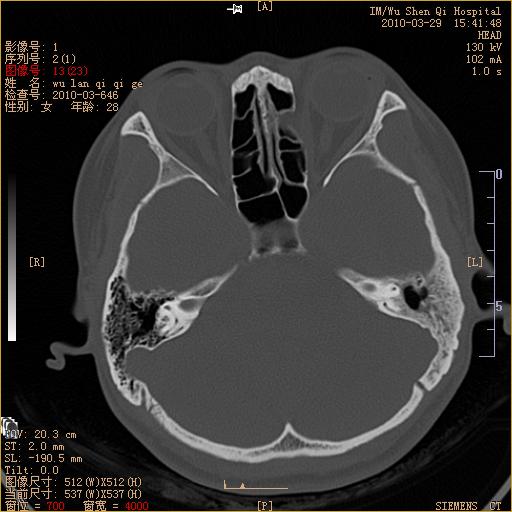

标题: CT25398:女,左耳流脓两年余,带有异物 [打印本页]

标题: CT25398:女,左耳流脓两年余,带有异物

左侧中耳乳突炎,不排除胆脂瘤形成。

左侧中耳乳突炎,胆脂瘤形成。

1)左侧慢性中耳乳突炎并肉芽肿(或胆脂瘤)形成。2)考虑左侧颞骨慢性炎症伴骨质增生硬化,不排除骨纤。